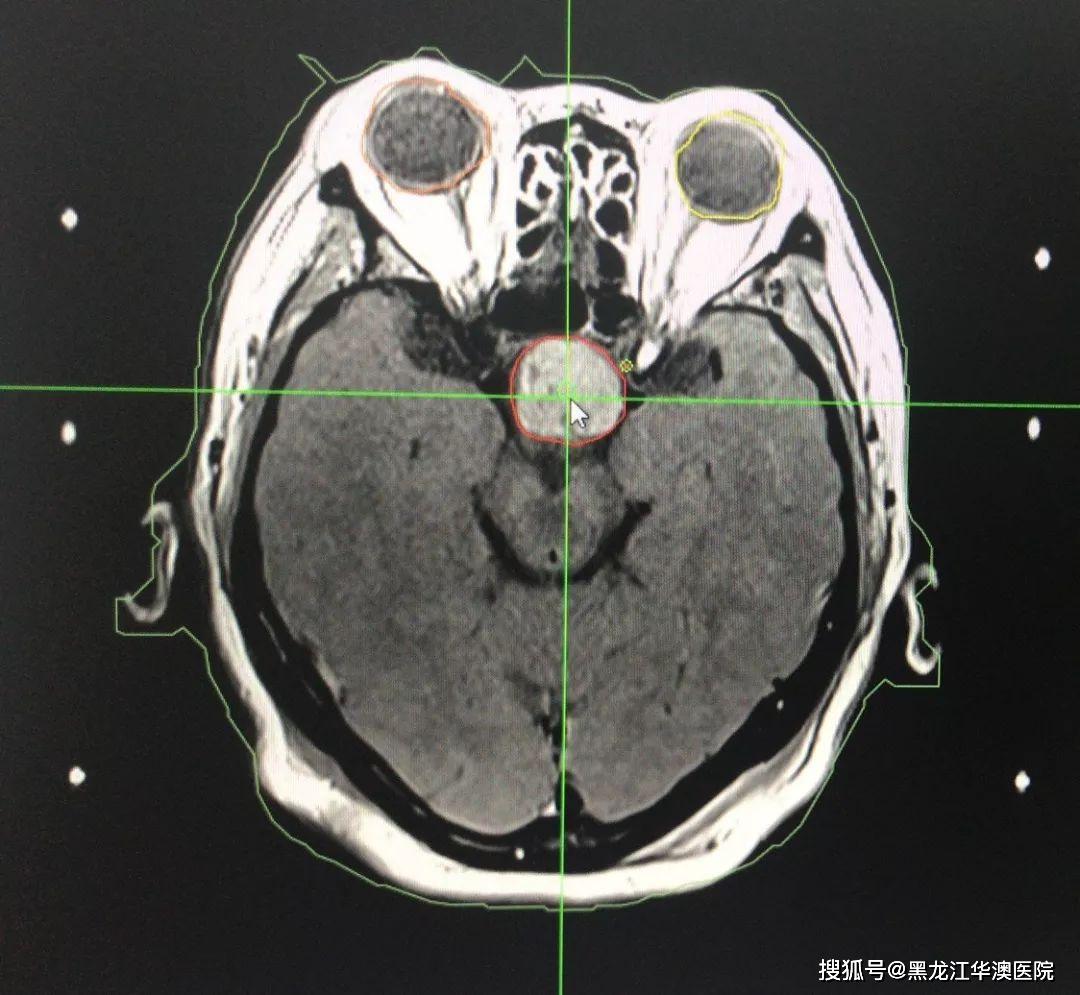

术中磁共振imri在复发性垂体瘤神经内镜手术中的作用

图片尺寸701x525